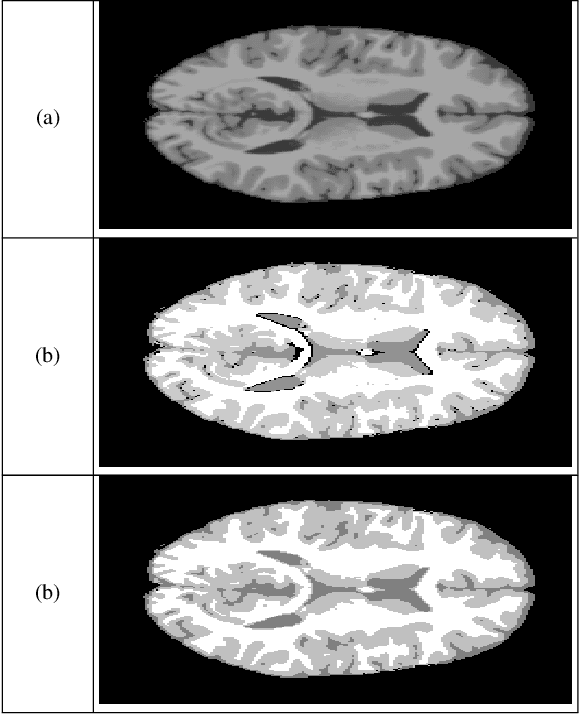

Abstract:Segmentation of medical images is an essential part in the process of diagnostics. Physicians require an automatic, robust and valid results. Hidden Markov Random Fields (HMRF) provide powerful model. This latter models the segmentation problem as the minimization of an energy function. Cuckoo search (CS) algorithm is one of the recent nature-inspired meta-heuristic algorithms. It has shown its efficiency in many engineering optimization problems. In this paper, we use three cuckoo search algorithm to achieve medical image segmentation.

Abstract:Image segmentation is the process of partitioning the image into significant regions easier to analyze. Nowadays, segmentation has become a necessity in many practical medical imaging methods as locating tumors and diseases. Hidden Markov Random Field model is one of several techniques used in image segmentation. It provides an elegant way to model the segmentation process. This modeling leads to the minimization of an objective function. Conjugate Gradient algorithm (CG) is one of the best known optimization techniques. This paper proposes the use of the Conjugate Gradient algorithm (CG) for image segmentation, based on the Hidden Markov Random Field. Since derivatives are not available for this expression, finite differences are used in the CG algorithm to approximate the first derivative. The approach is evaluated using a number of publicly available images, where ground truth is known. The Dice Coefficient is used as an objective criterion to measure the quality of segmentation. The results show that the proposed CG approach compares favorably with other variants of Hidden Markov Random Field segmentation algorithms.